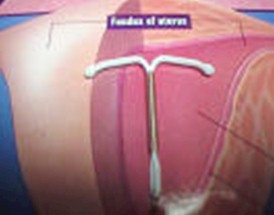

Un dispositivo intrauterino (DIU) es un dispositivo especial que se coloca dentro del cuerpo uterino. Hay más de un tipo de dispositivos. El dispositivo intrauterino se coloca en el útero a través de la vagina y protege del embarazo.

La colocación del Dispositivo intrauterino (DIU) lleva solo 10 a 15 minutos. El Dispositivo intrauterino (DIU) se colocará previa dilatación del cuello del útero, y luego pasando a través del mismo se lo ubica en el útero. Se lo coloca mediante un aplicador especial que lo mantiene cerrado y plano, hasta que llega al fondo del útero. Puede sentir contracciones durante la colocación, pero en general no son intensas.

La inserción no suele durar más de diez minutos y consiste en introducir el Dispositivo intrauterino (DIU) en una vaina de escaso diámetro a través del orificio cervical del útero, y conducirla con delicadeza hasta el interior de la cavidad uterina, en donde el médico descarga el Dispositivo intrauterino (DIU) una vez que considere que se encuentra ubicado en el lugar correcto. Posteriormente, se cortan los hilos a 2 cm del cuello uterino.

Cada vez que no se encuentren los hilos del dispositivo intrauterino en una revisión ginecológica de rutina se debe evaluar la posibilidad de pérdida o migración del Dispositivo intrauterino (DIU) dentro de la cavidad abdominal. Si en una ecografía ginecológica se observa que el interior del útero se encuentra vacío, se debe realizar una radiografía del abdomen porque el dispositivo puede haber perforado la pared uterina y encontrarse en la cavidad abdominal, lo que entraña riesgos importantes como el de infección del peritoneo (peritonitis), que es la capa que envuelve los órganos abdominales.